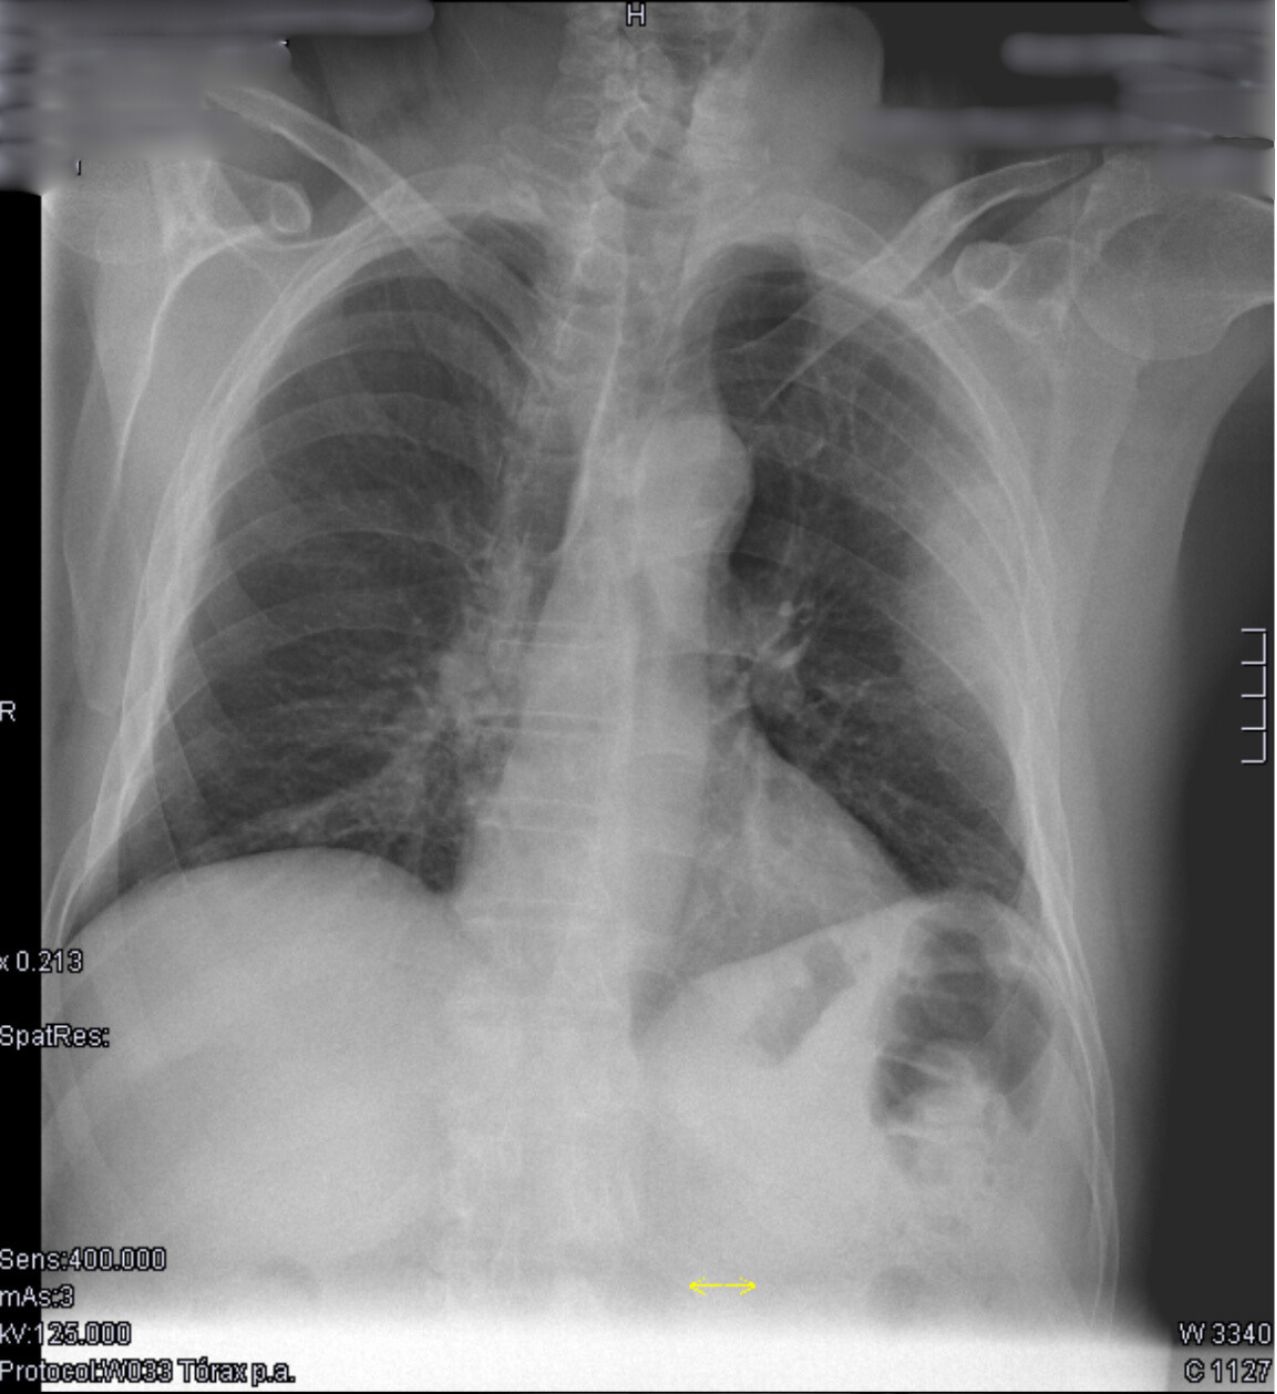

Rx PA de tórax